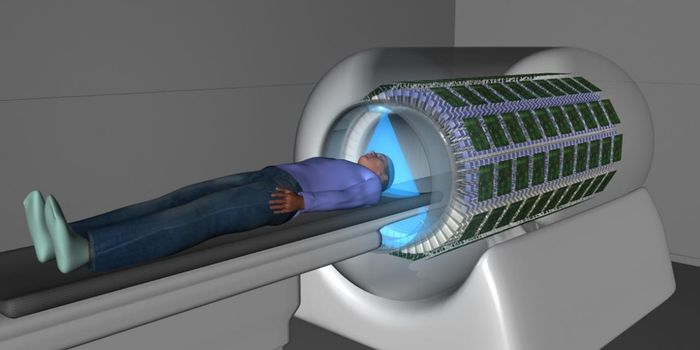

JUN 07, 2020Chemistry & PhysicsScientists from the University of Nottingham have published their most recent developments on a wearable 49 channel brai ...